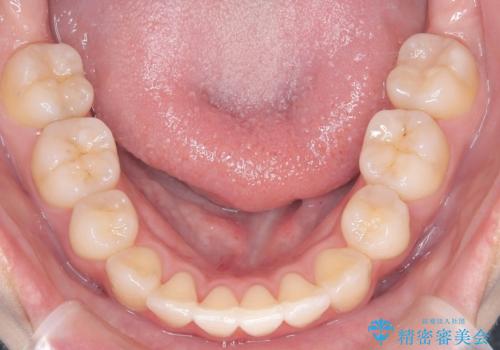

- 「歯のでこぼこを治したい」を主訴に来院された患者様です。 上下ともに、歯のでこぼこが強く、上下左右4の抜歯をし、ワイヤー矯正で治療を行いました。

かなり綺麗に並ぶ事ができ大変満足していただけました。

叢生量がかなり多かったのですが、歯肉退縮も失活歯も無くとても綺麗な歯並びになりました。